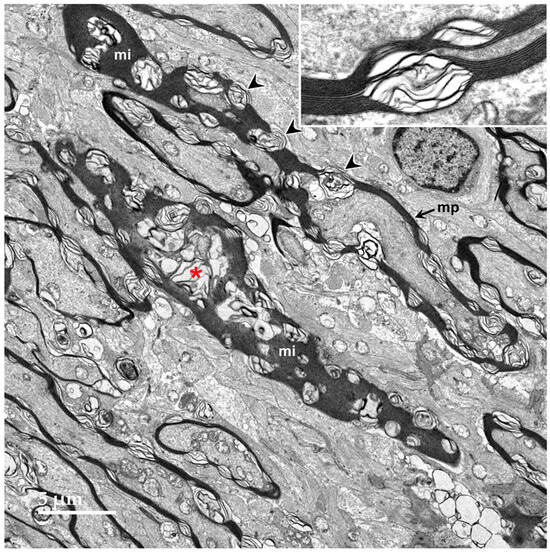

3.1. Microscopic Findings